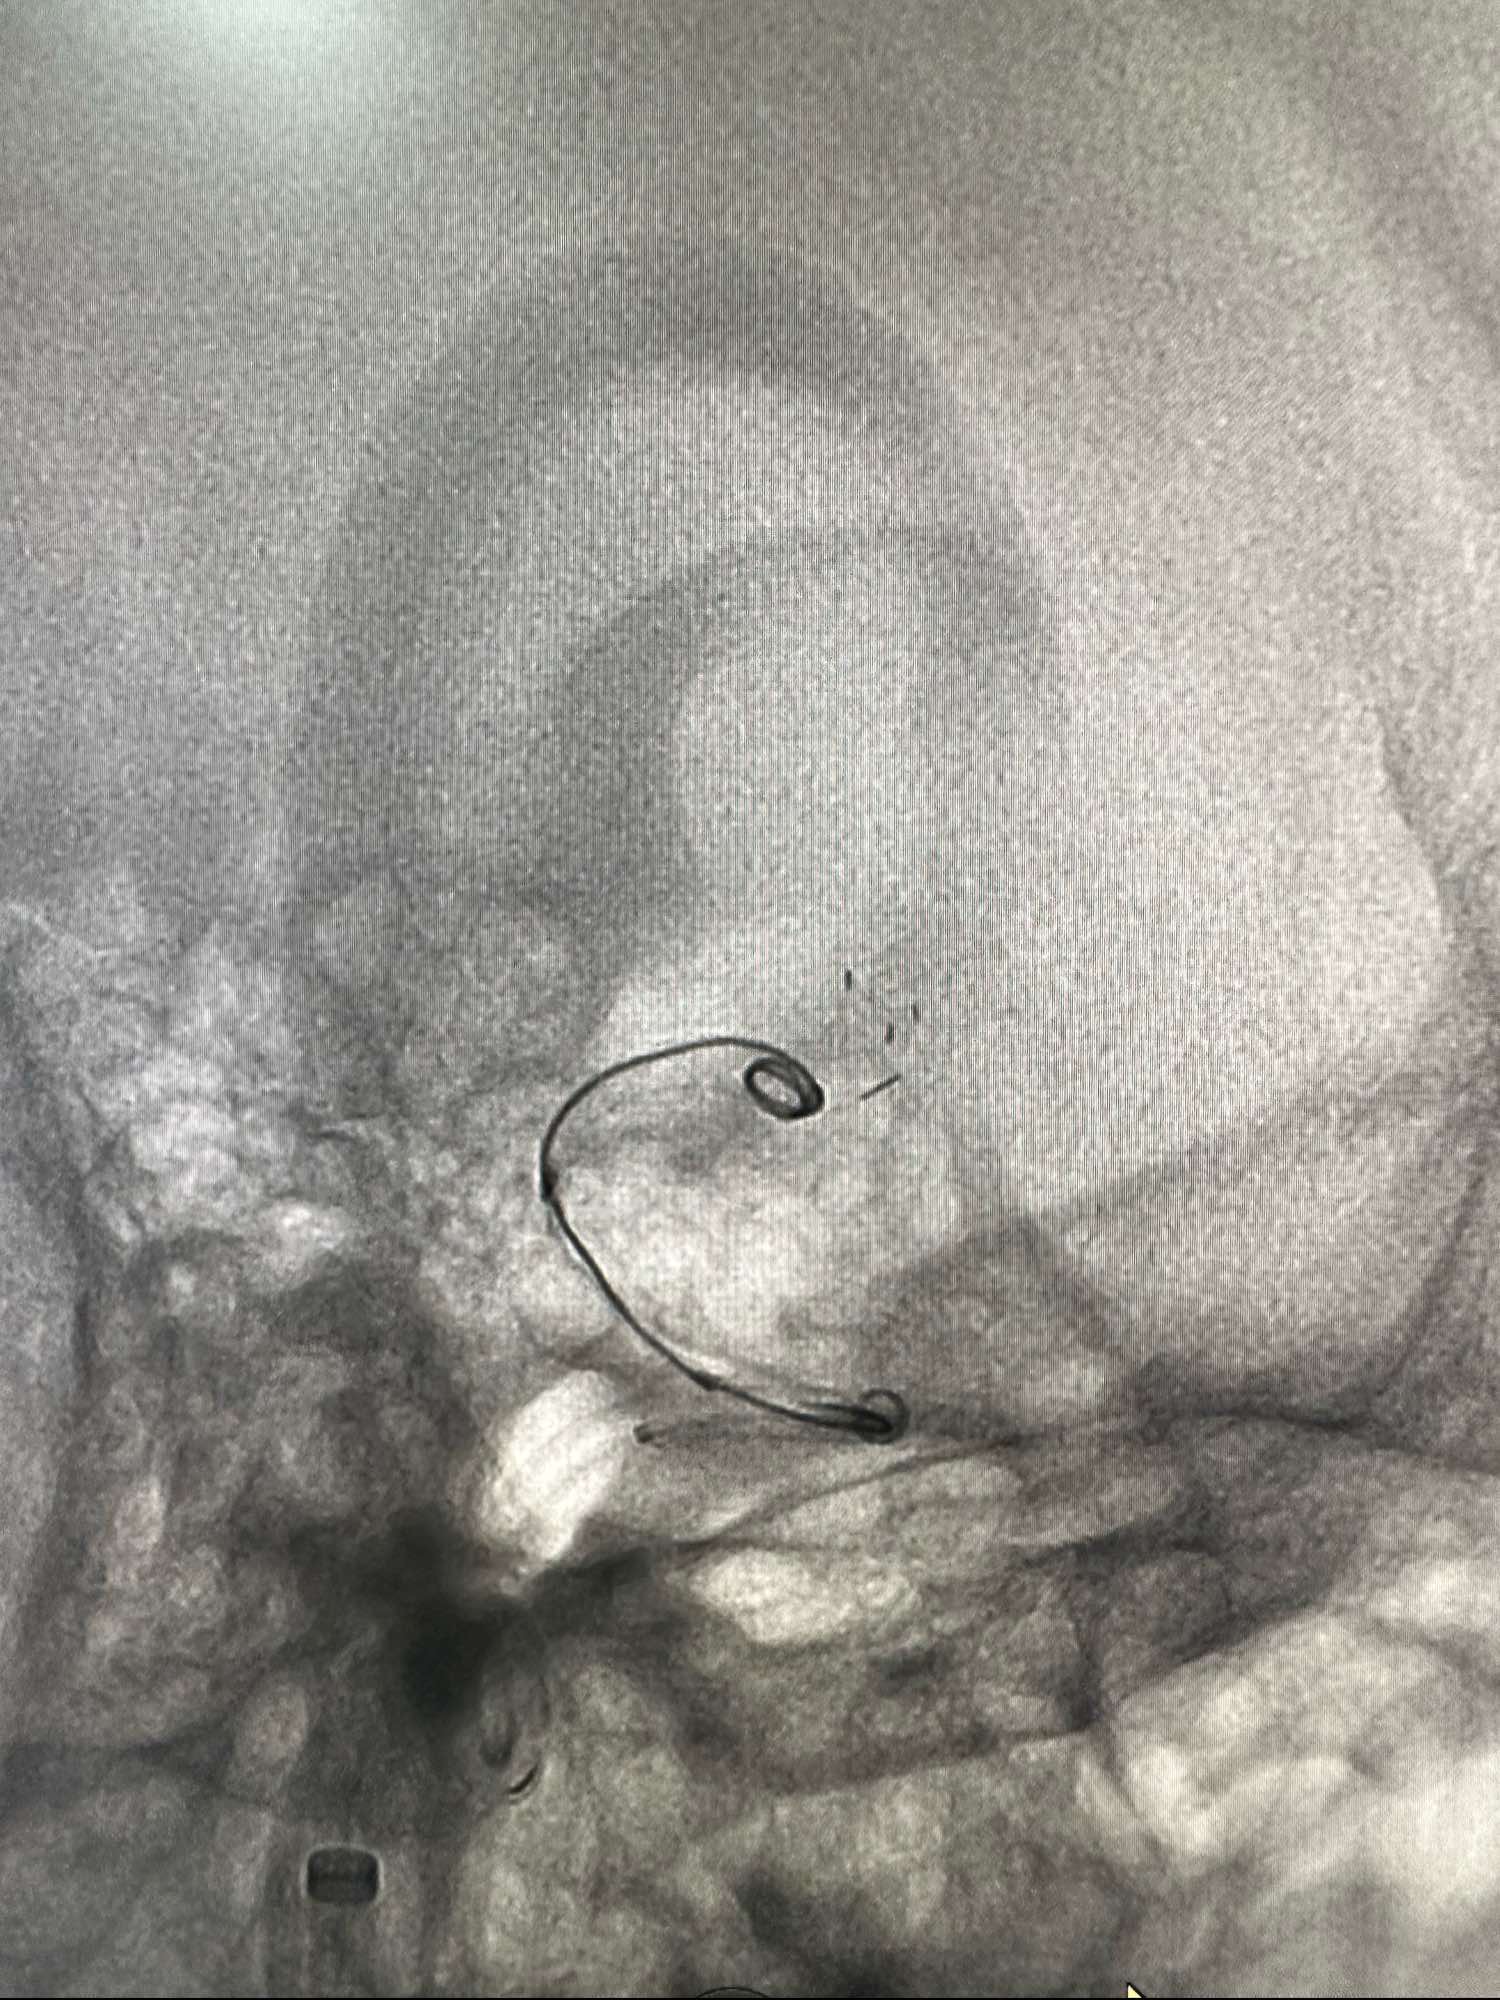

圈的形态

术中发现有血栓,动脉内直接给予新维林8ML,并静脉内持续泵入4ML再次造影见血栓已经完全消失

侧位,术后患者完全清醒,未见特殊异常